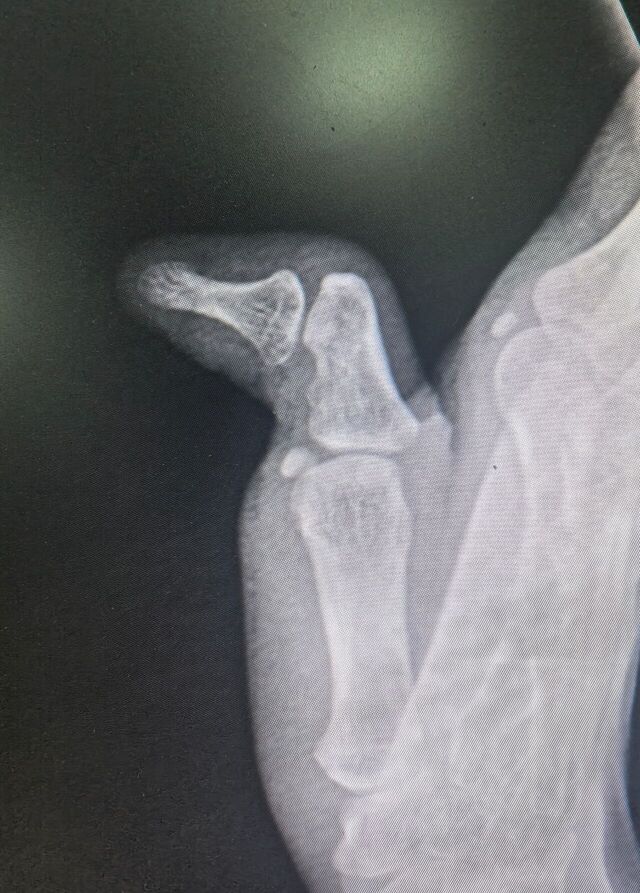

拇指先天畸形

mmexport1754487711297.jpg

mmexport1754487742008.jpg